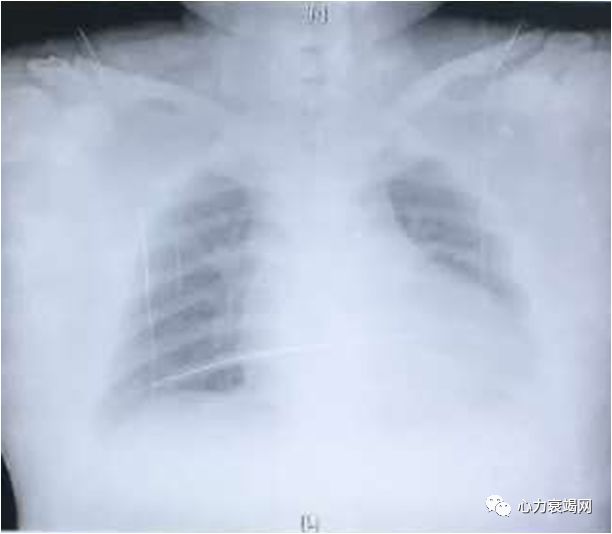

➤ 胸片

左房室增大

伴左心功能

不全改变